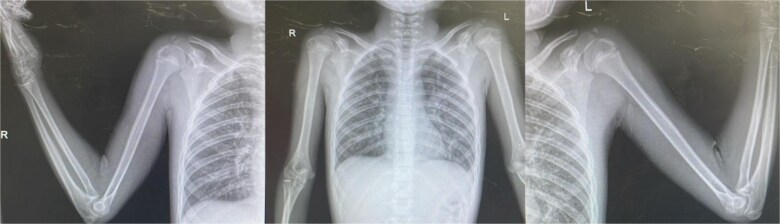

性早熟是一种罕见的情况,特别是在男孩中,其特点是第二性特征的早期发展。本病例报告介绍了一名来自危地马拉农村的5岁男性,他表现出性成熟加速的迹象,包括Tanner期IV生殖器、阴毛和面部毛发以及骨龄提前。经评估,诊断与慢性营养不良和社会心理压力等环境因素有关,这些因素可能导致下丘脑-垂体-性腺轴过早激活。在资源匮乏的环境中,贫困、获得医疗保健的机会有限和营养缺乏等因素会严重影响生长发育,导致性早熟等非典型症状。这一案例突出了在诊断和管理青春期时考虑环境因素和健康的社会决定因素的重要性,特别是在服务不足的人群中。

Precocious puberty is a rare condition, particularly in boys, characterized by the early development of secondary sexual characteristics. This case report presents a 5-year-old male from rural Guatemala who exhibited signs of accelerated sexual maturation, including Tanner stage IV genitalia, pubic and facial hair, and advanced bone age. After evaluation, the diagnosis was associated with environmental factors such as chronic malnutrition and psychosocial stress, which likely contributed to the premature activation of the hypothalamic-pituitary-gonadal axis. In low-resource settings, factors like poverty, limited access to healthcare, and nutritional deficiencies can significantly impact growth and development, leading to atypical presentations of conditions like precocious puberty. This case highlights the importance of considering environmental factors and social determinants of health when diagnosing and managing puberty, especially in underserved populations.